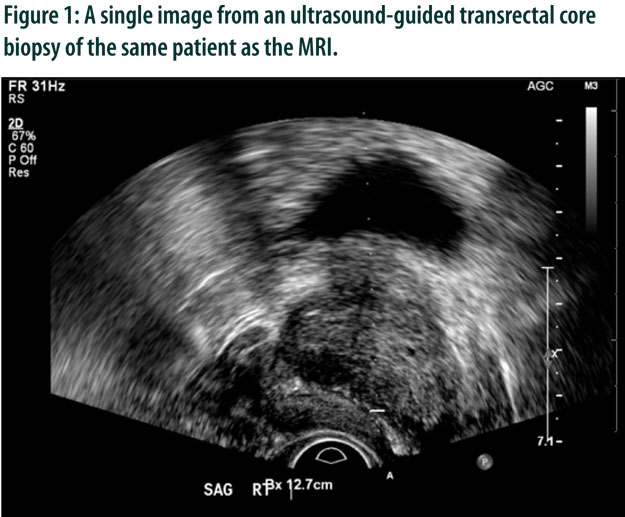

Prostate Cancer Imaging: Ultrasound, CT, MRI, and Nuclear Medicine Techniques

Abstract: Prostate cancer is a common cancer in men worldwide, and early detection is key to improved patient outcomes. Diagnosis typically involves a combination of clinical examination, prostate-specific antigen blood testing, and imaging studies. Radiology plays an important role, aiding in treatment planning, confirming the diagnosis by directing biopsy, staging the patient, and following treatment course. Imaging modalities for prostate cancer diagnosis include ultrasound, CT, nuclear medicine, and MRI. While MRI is the most sensitive imaging modality, ultrasound is still the preferred modality for measuring the prostate volume. Prostate-specific membrane antigen PET imaging has shown to have superior sensitivity and specificity compared to conventional imaging modalities in the detection of prostate cancer, especially in the context of low PSA. Clinical pearls include performing ultrasound-guided biopsy under local anesthesia to improve patient comfort, and the use of fusion MRI and ultrasound images to facilitate MRI/TRUS fusion-guided biopsy.

Ultrasound-guided biopsy is a minimally-invasive procedure that involves inserting a needle through the rectum via an ultrasound probe guide and into the prostate gland. It is performed under local anesthesia and patients are discharged the same day after a short period of observation in the radiology department.

MRI and ultrasound images can be fused to facilitate MRI/TRUS fusion-guided biopsy, which improves the accuracy of the biopsy procedure.